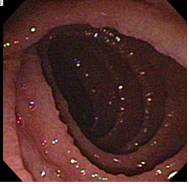

35 year old male presents with colicky abdominal pain and diarrhea 4-5 times a day for the past 2 years. What is his differential and diagnosis based on the colonoscopy image below?

Celiac sprue:

- Antibodies to gliadin

- Distal duodenum, proximal jejunem

- Loss of villi on histology

Malabsorption of:

- Vitamin K–> hemorrhagic diathesis

- Iron deficiency

- associated with dermatitis herpetiformis

- Increased risk of malignancy (T-cell lymphoma)

Colonoscopy= celiac sprue; see small-bowel scalloping

Testing:

- Gluten-containing diet before biopsy, response to gluten-free diet

- Serology: Anti-tTG IgA (anti-tissue transglutaminase; high sensitivity, specificity), serum IgA (to rule out IgA deficiency= false negative), anti-endomysial, HLA testing of DQ2/DQ8